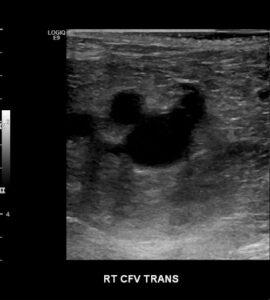

Duplex Diagnosis of Lower Extremity Venous Thrombosis

Master the essentials of Duplex Ultrasound for Lower Extremity Venous Thrombosis diagnosis. This comprehensive course covers DVT pathophysiology, technical aspects of duplex imaging, spectral Doppler flow analysis, and differentiating acute from chronic thrombosis. Enhance your diagnostic accuracy today!

Understand technical aspects of duplex ultrasound for diagnosis of lower extremity venous thrombosis.

Understand imaging and location-specific features related to diagnosis of lower extremity venous thrombosis.